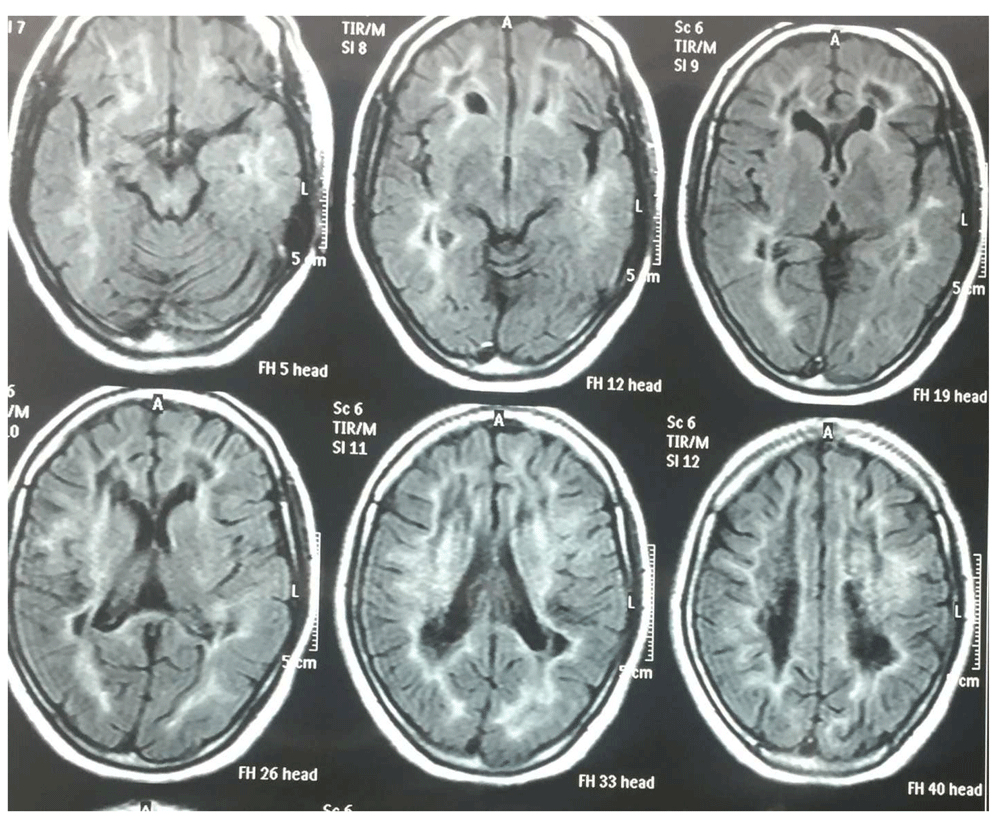

Her MRI brain scan was remarkable for diffuse leukodystrophy (Figure 1 and Figure 2). Her hormonal assays were consistent with premature menopause (Table 1). An ultrasound of her abdomen and pelvis was remarkable for small ovaries and uterus. Her lumbar puncture results were normal and there were no oligoclonal bands in her cerebrospinal fluid (CSF). She underwent genetic tests including sequence analysis and polymerase chain reaction (PCR), which demonstrated a point mutation in the EIF2B4 gene. Thus, she was diagnosed as a second case of VWM from the same family of 12 siblings and 2 parents. None of the family members were screened due to affordability issues.

The diagnostic workup includes MR imaging of the central nervous system which demonstrates diffuse and cystic degenerative loss of the deep cortical white matter and U-fibers. The grey matter is preserved3,5,6. This is due to a mutation in EIF2B which causes impairment of protein synthesis under conditions of cellular stress like infection, trauma, intense emotions and surgery. The genetic tests confirm the diagnosis6. Those females who live into adulthood develop ovarian failure2,4,6. Interestingly, according to our literature search, primary testicular failure has not been described in any reported case of affected males .